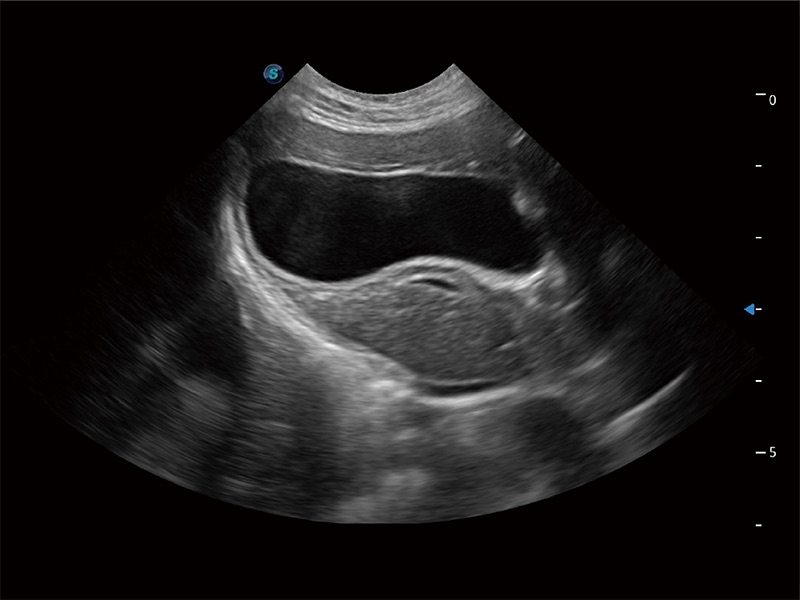

ProPet 80 配备了丰富的心脏探头群、先进的成像技术和专业的心脏测量工具,可帮助动物医生为不同体型和生理结构的动物提供心脏和心肌功能的全面评估。

一键自动识别膀胱壁及自动测量膀胱容积,不受膀胱形状和大小的限制,帮助医生快速精准获得测量的数据。